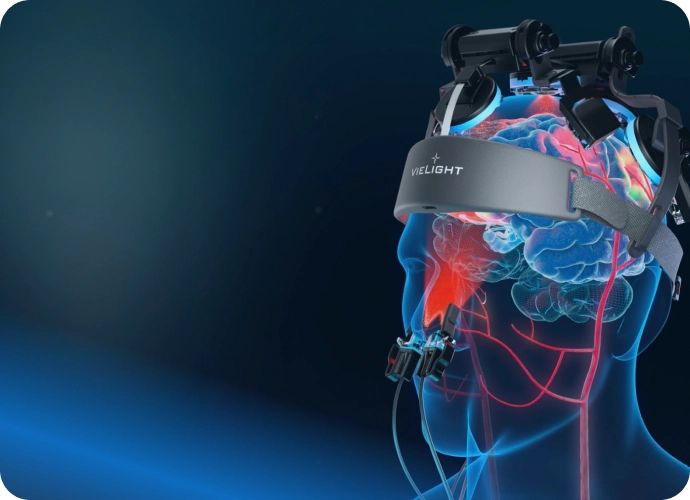

| Targeted Areas | Cerebellum, Occipital lobe, Thymus gland, Nasal vasculature |